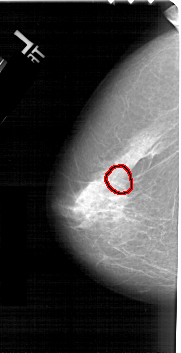

A_1378_1.LEFT_MLO

FILE: A_1378_1.LEFT_MLO.OVERLAY

TOTAL_ABNORMALITIES 1

ABNORMALITY 1

LESION_TYPE CALCIFICATION TYPE PLEOMORPHIC DISTRIBUTION CLUSTERED

ASSESSMENT 4

SUBTLETY 4

PATHOLOGY BENIGN

TOTAL_OUTLINES 1

BOUNDARY